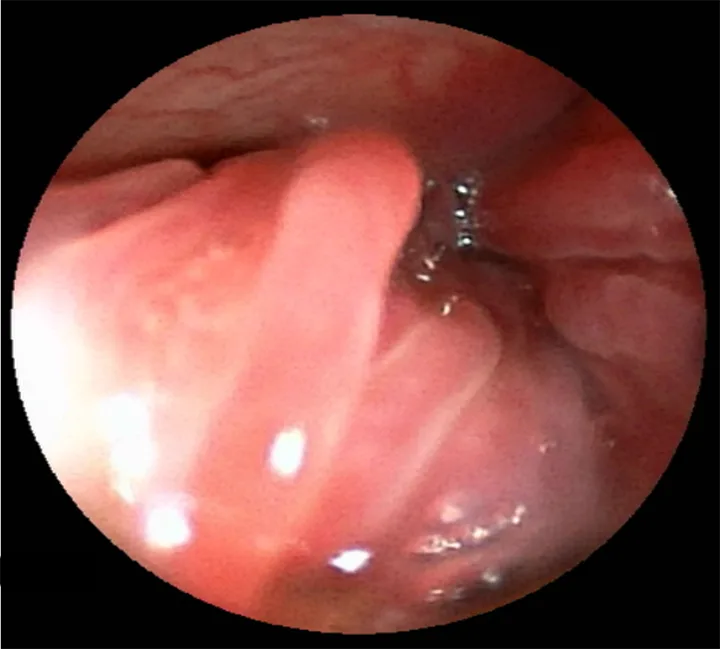

A rigid or flexible rhinoscope can visualize nasal passages, and flexible rhinoscopy can achieve retroflexed views of the nasopharynx (Figure 3). Rhinoscope-guided biopsy may be possible, depending on the size and type of scope compared with the patient. Blind biopsy can be performed if guided biopsy is not possible and should ideally be based on CT and/or rhinoscopy images.

Rhinoscopy image of turbinates in a dog.

FIGURE 3

Rhinoscopy image of mildly erythematous turbinates in the left nasal cavity of an 11-year-old spayed Australian shepherd with lymphoplasmacytic rhinitis